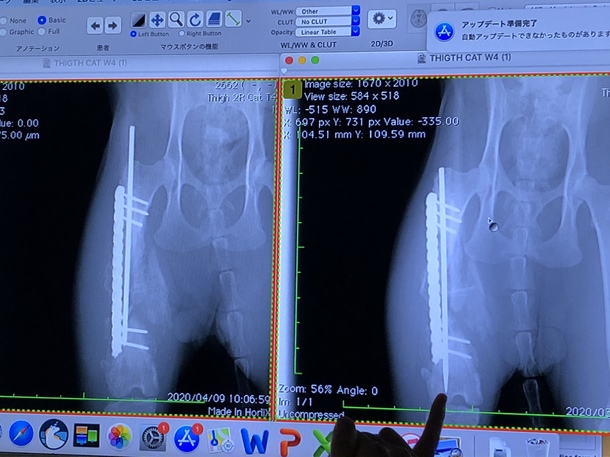

右が手術後すぐ

左が現在のワカバくんのレントゲンです。

現時点で

中のピンが上にずれてます💦

今後ケージ生活でしばらく安静にし

次の病院までに骨がもう少しくっつけば

ピンは抜いてしまうそうです。

しかし、ピンが外に突き出てしまう可能性もあるとか…想像しただけでも恐ろしいです。

骨の状態次第では再度ピンの入れ直し手術になります。

ワカバ君にとって痛みの少ない方法が1番だと思うので

ワカバ君の治癒力にかかってます。

次の病院は10日後になりました。